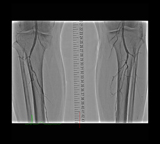

下肢動脈CT

当院では、80列(AquilionPRIME:CANON社製)と2018年12月に導入された320列(Aquilion ONE:CANON社製)の2台体制で運用しています。

320列CT装置は、現在のMDCT装置の中では検出器が最大多列であり、寝台移動することなく1回転で16cmの撮影ができます。さらに回転速度が最速0.275秒であることから小児撮影や冠動脈撮影など高速かつ低被ばくが望ましい患者様・部位の撮影に有用です。特に冠動脈撮影では、高心拍や不整脈の方でも安定した画像を撮影することができます。また、広範囲の撮影を必要とする救急領域では、160列ヘリカル撮影により160cmの範囲を約10秒で撮影することができるため息止めや静止が困難な患者様にも幅広くお使いいただけます。

さらなる低被ばく・高画質を目指し画像再構成法も進化しています。まず、FIRSTと呼ばれる再構成法では真の逐次近似再構成法であるためノイズを除去しながら空間分解能の向上が実現されています。たとえば検診目的の低線量胸部撮影や小児撮影、腕おろし検査時などの画質向上や血管ステントの形状の先鋭化、プラークの境界明瞭化による内腔診断能向上に貢献します。

そして当院の装置は人工知能技術を用いた画像再構成法「AiCE」を搭載しています。AiCEはディープラーニングを用いて設計されたノイズ成分とシグナル成分を識別する処理で、分解能を維持したままノイズを選択的に除去する再構成技術です。

高品質FIRSTを継承した画質を取得可能であり、空間分解能の向上や大幅なノイズ低減効果が得られます。特に低コントラスト領域での高いノイズ低減と粒状性を維持し、低線量であっても安定した高画質な画像を提供することができます。

その他、両方の装置に搭載されている金属アーチファクト低減再構成法SEMARは、ヘリカルスキャンにも適応できるようになり、広範囲撮影やより多くの撮影プロトコルで対応可能になりました。

また両装置とも開口径が78cmと広く、検査における圧迫感の軽減や、撮影体位の柔軟性も高く、リラックスした状態で検査を受けていただけます。2台のマルチスライスCTを有効に活用し、地域医療に貢献できればと考えています。